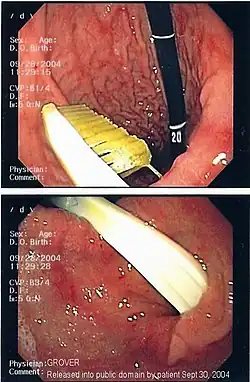

| A foreign body - in this case a swallowed toothbrush - located in the stomach cavity by using an endoscope. | |

One of the most common locations for a foreign body is the alimentary tract. It is possible for foreign bodies to enter the tract either from the mouth,[1] or from the rectum.[2]

Endoscopic foreign body retrieval is the first-line treatment for removal of a foreign body from the alimentary tract.[10]